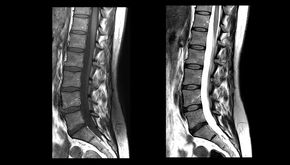

Andrés24 ene 20222 Min. de lectura¿Existe relación entre el hallazgo en pruebas de imagen y daño en los tejidos?